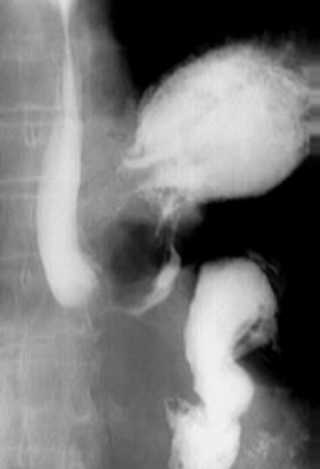

Neoplasm malign gastric vegetant

Neoplasm malign gastric infiltrativ

Neoplasm malign gastric ulcerant